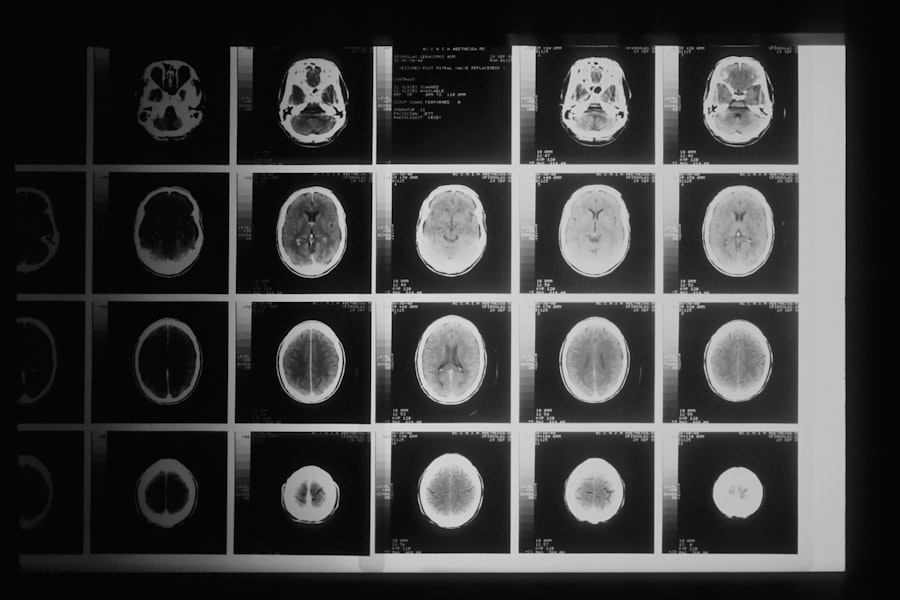

Delving into the science behind brain power reveals a complex interplay of neurons, neurotransmitters, and electrical impulses that work together to create thoughts, emotions, and actions. Your brain consists of approximately 86 billion neurons, each connected by synapses that transmit signals. These connections are crucial for communication within the brain and between the brain and the rest of your body.

Mindfulness and meditation have gained recognition for their profound impact on brain health and cognitive function. These practices encourage you to focus on the present moment, fostering greater awareness and reducing distractions. Research has shown that regular meditation can lead to structural changes in the brain, including increased gray matter density in areas associated with memory, emotional regulation, and self-awareness.